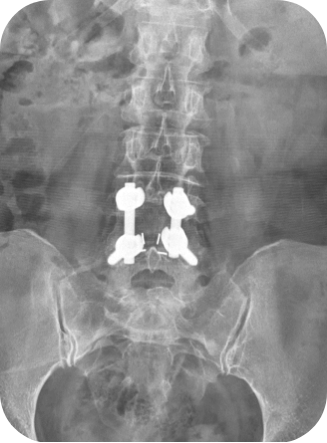

척추유합술(피질골 나사못을 이용한 유합술)

척추 분절의 불안정성이 확인 되면 나사못과 뼈유합을 이용한 고정술이라는 수술을 택할 수 있습니다. 일반적으로 큰 수술이고 긴 시간과 많은 출혈량이 문제이지만 저희 좋은 아침병원에서 시행되는 유합술은 부분마취하 최소침습의 방법으로 빠른 회복과 부작용의 최소화에 힘쓰고 있습니다.

- 불안정성을 동반한 추간판탈출증, 척추관협착증, 전방척추전위증